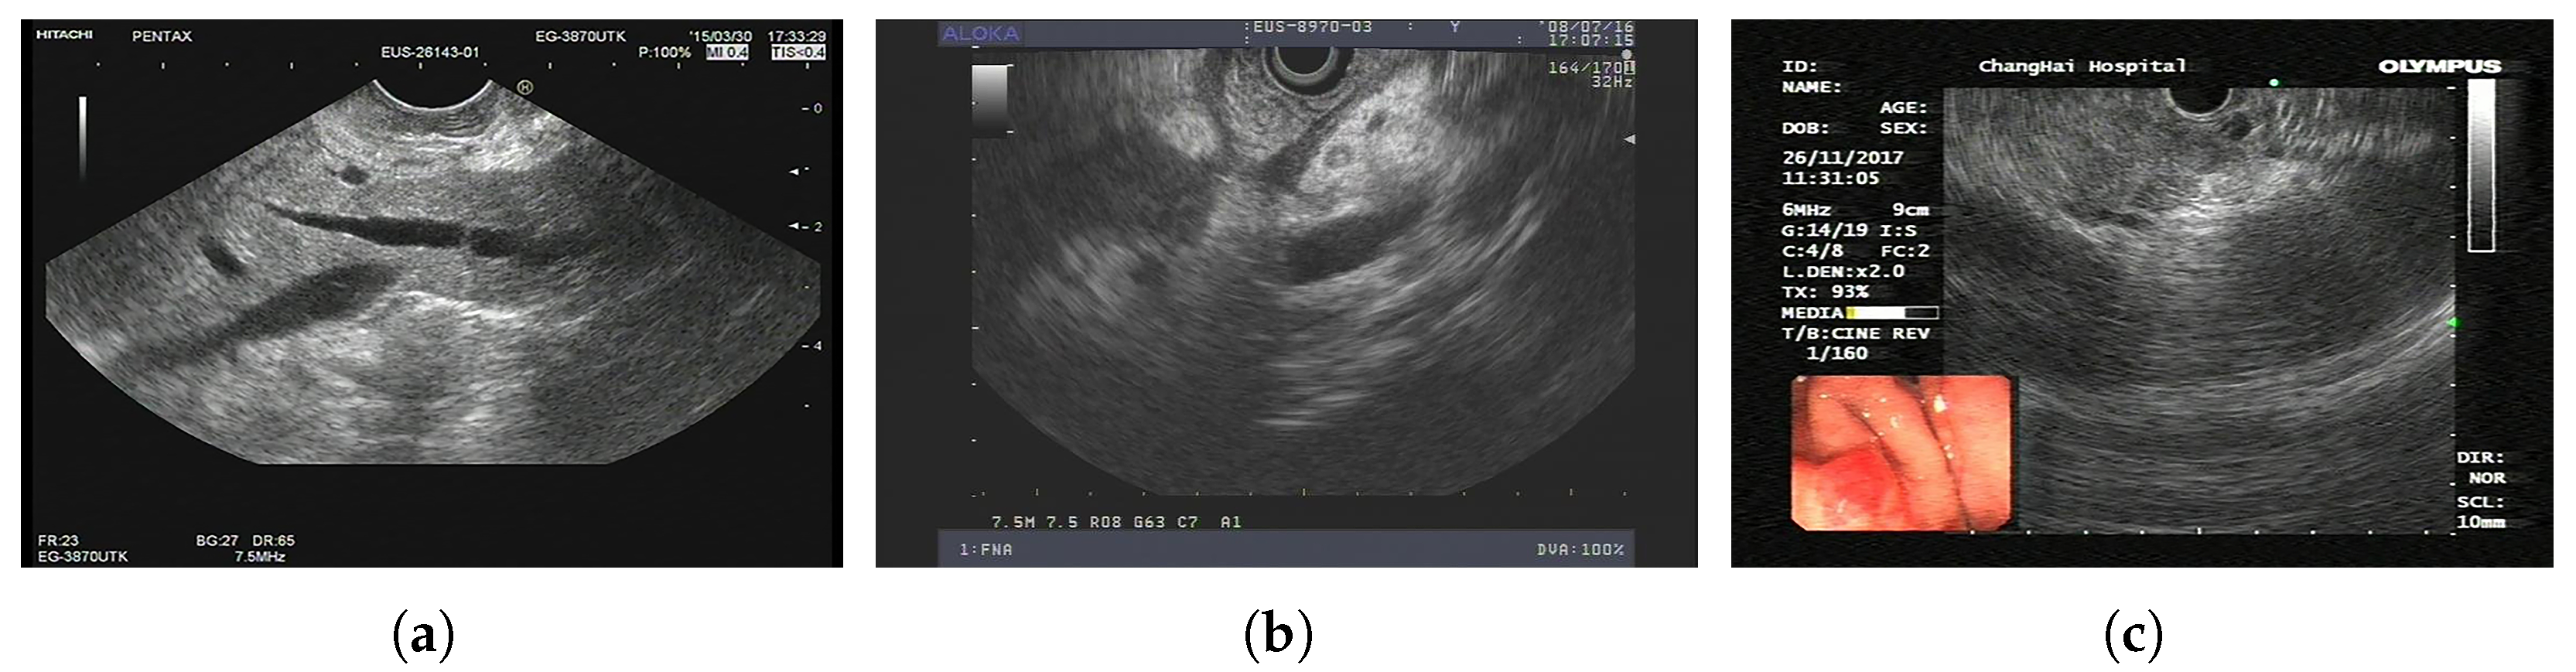

The dataset is based on EUS and consists of 420 patients and 3500 images. Its task is to classify PCs and non-PCs. Experienced physicians annotated these 3500 images with category labels. In addition, there are 8000 unlabeled images for pretraining. Sample images from LEPset are shown in Figure 4, with images labeled as PC or non-PC and unlabeled data.

Figure 4.

LEPset sample data: (a) labeled non-PC, (b) labeled PC, and (c) unlabeled image.